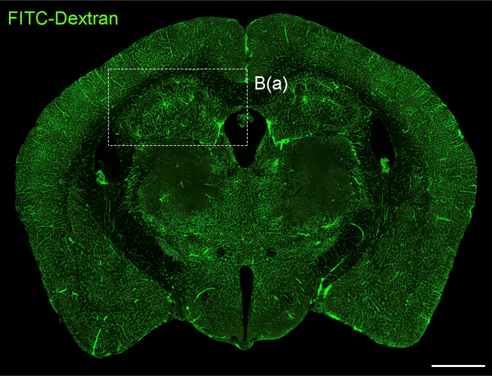

신경면역학 실험실(이찬희 교수님)

biomedical_JW_MS_K2WT001_S